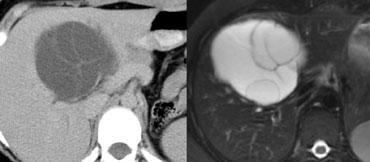

U máu gan trên CT không tiêm thuốc, thì động mạch muộn, thì tĩnh mạch cửa muộn và thì cân bằng. Lưu ý tỷ trọng của u máu tương đương với hồ máu trong tất cả các thì (mũi tên).

Hồ máu và U máu gan

Thông thường khi đánh giá các tổn thương ngấm thuốc, tỷ trọng của tổn thương luôn được so sánh với tỷ trọng của nhu mô gan.

Tuy nhiên, đối với u máu gan, không nên so sánh tỷ trọng của tổn thương với gan mà phải so sánh với hồ máu.

Điều này có nghĩa là các vùng ngấm thuốc trong u máu phải tương đương với tỷ trọng của các mạch máu tương ứng (hồ máu) ở mọi thời điểm.

Vì vậy, trong thì động mạch, các phần ngấm thuốc của tổn thương phải có giá trị tỷ trọng gần bằng với động mạch chủ đang ngấm thuốc, trong khi ở thì tĩnh mạch cửa phải tương đương với sự ngấm thuốc của tĩnh mạch cửa.

Nếu tỷ trọng không tương đương với hồ máu trong tất cả các thì tiêm thuốc, hãy loại bỏ chẩn đoán u máu gan.

Hình bên trái là một u máu gan điển hình.

Lưu ý rằng trên CT không tiêm thuốc, tỷ trọng của khối u tương đương với tỷ trọng của các mạch máu.

Trong thì động mạch, tỷ trọng tương đương với hồ máu và gần bằng với động mạch chủ.

Trong thì tĩnh mạch cửa, tỷ trọng tương đương với tĩnh mạch cửa.

Trong thì cân bằng, tỷ trọng ngấm thuốc tương đương với các mạch máu.

Cuối cùng tổn thương sẽ trở nên đồng tỷ trọng với gan, nhưng chỉ vì các mạch máu cũng trở nên đồng tỷ trọng với gan.

Điều này không liên quan đến tỷ trọng của bản thân nhu mô gan.

Vì vậy, hãy nghĩ đến hồ máu thay vì gan khi nghĩ đến u máu gan.